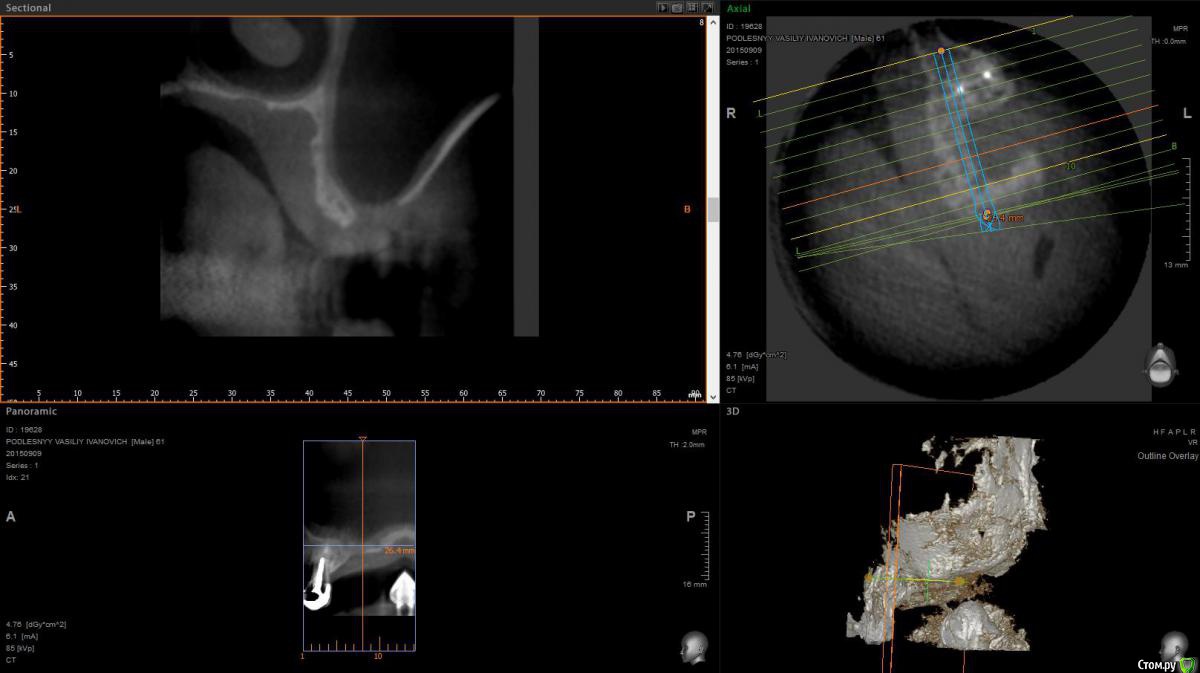

krokomot Опубликовано 11 сентября, 2015 Поделиться Опубликовано 11 сентября, 2015 Все слишком тонко, вряд ли остеопластика ту поможет ИМХО 1 1 Ссылка на комментарий

diesel87 Опубликовано 11 сентября, 2015 Поделиться Опубликовано 11 сентября, 2015 Делайте синус через это окно, если не получится, стандартное окно на передней стенке вырезайте, перфу бы закрыл чем нибудь по-жестче, ПТФЕ или титановой сеткой. Вы сами то как планируете? 3 Ссылка на комментарий

Bier Опубликовано 12 сентября, 2015 Поделиться Опубликовано 12 сентября, 2015 по большому счету тут обычный синус нужно сделать и возможно прикрыть окклюзионное окно чем-то жестким или полужестким Ссылка на комментарий